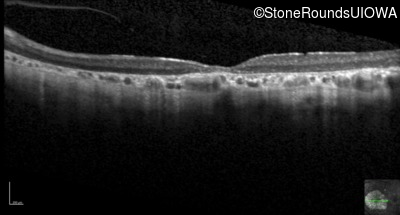

Optical Coherence Tomography - Left - 20/160 sc

Exemplar / OCT Stack

OCT Stack